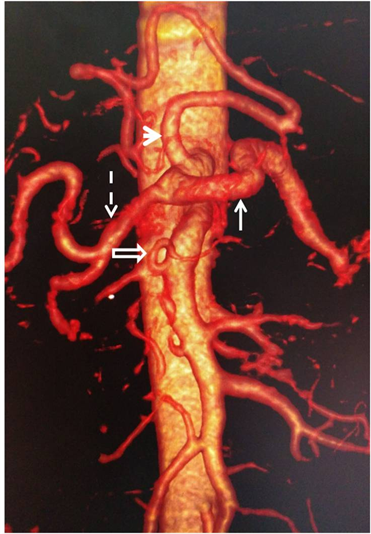

As for quadrifurcation, there were two types. One had a gastro-duodenal artery (Figure 6) and another had a right hepatic artery associated with a left hepatic artery (Figure 7). One patient among the 3 carriers of a collateral corresponding to a left hepatic artery presented two singularities: a trifurcation made

Figure 6. Enhanced abdominal CT-scan showing on 3D reconstruction, a quadrifurcation of celiac trunk, with a common hepatic artery (thin arrow), a stomachic coronary artery (hollow arrow), a splenic artery (thick arrow) and a gastro-duodenal artery (arrow head).

of two right hepatic arteries and the splenic artery (Figure 8), a “pseudo-arc” of Buhler, stretched between the celiac trunk and the inferior mesenteric artery (Figure 9). Table 2 summarizes all the AVs encountered with their frequencies.

Figure 8. Enhanced abdominal CT-scan on 3D reconstruction showing two right hepatic arteries (arrow head and hollow arrow), a left hepatic artery of collateral disposition (thick arrow), a splenic artery (thin arrow) and a gastric artery originating from superior mesenteric artery (hatched arrow).

Figure 9. Enhanced abdominal CT-scan on 3D reconstruction showing a “pseudo-arch” of Buhler indicated by a thin arrow whose proximal end is celiac (arrow head) and the distal end is inferior mesenteric (thick arrow).